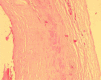

True aneurysms of hand arteries are rare. I present a case of a true saccular aneurysm of the distal radial artery in a 65-year-old woman with no history of trauma. The CT angiography, intraoperative features, operative procedure, histopathological examination and literature review are presented and discussed.